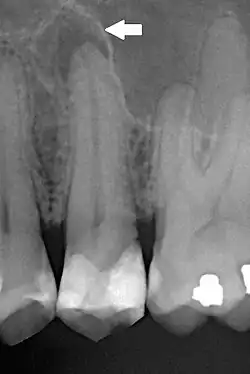

Aspectos radiográficos

A PA pode inicialmente não apresentar nenhum aspecto radiográfico, apenas sintomatologia clínica, em sua fase mais inicial.[1][2] Posteriormente, pode evoluir para apresentar espaçamento do espaço do ligamento periodontal.[1][2] A PA crônica tende a se apresentar como uma rarefação óssea difusa associada ao dente afetado, com perda da continuidade da lâmina dura.[1]

O diagnóstico diferencial radiográfico inclui:[1]

- Granuloma periapical;

- Cisto radicular;

- Cisto dentígero;

- Queratocisto odontogênico;

- Ameloblastoma;

- Displasia cemento-óssea.